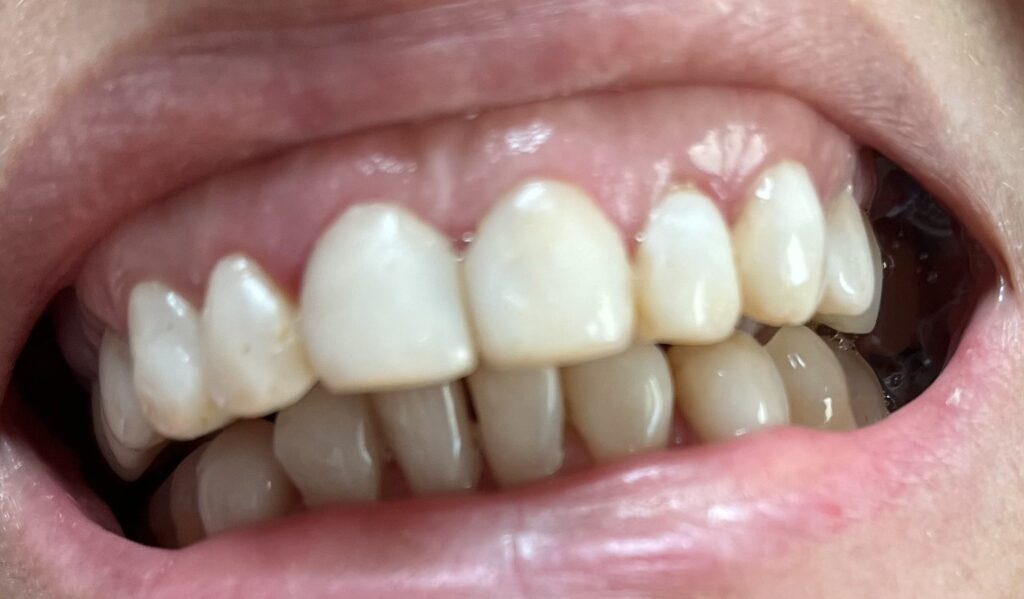

Każdy uśmiech ma swoją historię – my pomagamy ją opowiedzieć na nowo. Dzięki indywidualnie dobranym planom leczenia przywracamy pacjentom nie tylko piękny wygląd zębów, ale również komfort i funkcjonalność w codziennym życiu. Poniżej przedstawiamy wybrane przypadki metamorfoz, które pokazują, jak zaawansowana protetyka, nowoczesne techniki odbudowy oraz precyzyjne leczenie endodontyczne potrafią całkowicie odmienić uśmiech.